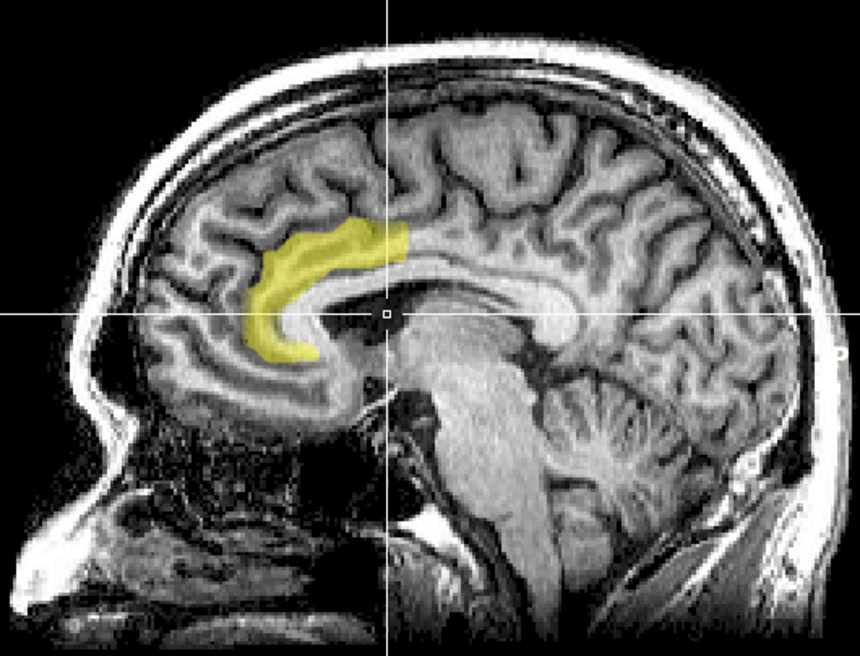

心理的な要因が身体の感覚に影響を与えているとも言われており、これまでの研究では、プラセボ効果が脳の「前帯状皮質(ぜんたいじょうひしつ)」に関連していることまでは解明されていた。

ここは痛みの処理に関連する領域で、プラセボ効果が発現するとき活発になるのだ。

研究チームはこの時のマウスの脳内を観察してみた。注目されたのは、「前帯状皮質の吻側部(ぜんたいじょうひしつ・ふんそくぶ)」と「橋核(きょうかく)」との間にある領域だ。

このことから、前帯状皮質吻側部と橋核をつないでいる領域が、プラセボ効果に重要な役割を果たしていることが推測できる。

この画像を大きなサイズで見る橋核にはオピオイド受容体が豊富に存在することにも注目されており、この領域が痛覚耐性に関与している可能性を示す証拠となるという。